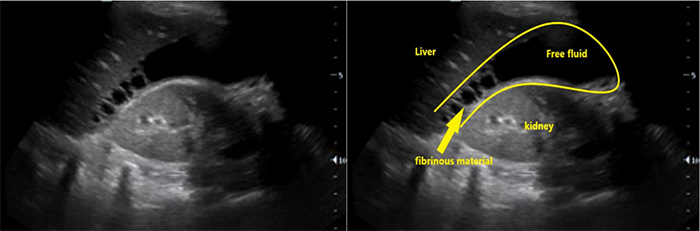

- Ascites (Fig. 6)

- Ascites is a common finding in many disease entities however in the patient with HIV from a TB endemic area, it is highly suggestive of TB.

- With or without fibrinous debris: OR 2.221

- Without fibrinous stranding: PPV= 73% NPV = 33%18

- With fibrinous stranding: PPV = 86% NPV= 41%18

Figure 7. Fibrinous ascites in pelvis sagittal view

Figure 8. RUQ free fluid with fibrinous stranding and hyperechoic liver lesions